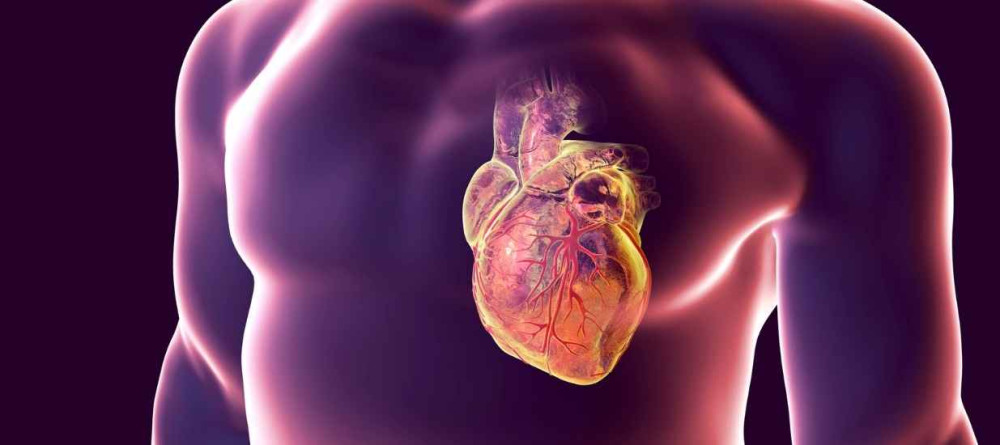

Mitral kapak yetmezliği kalp sağlığıyla ilgili ciddi bir durumdur. Bu durumun belirtileri, risk faktörleri, tanı yöntemleri ve tedavi seçenekleri hakkında...